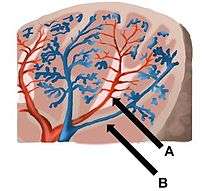

The spleen synthesizes antibodies in its white pulp and removes antibody-coated bacteria and antibody-coated blood cells by way of blood and lymph node circulation. A study published in 2009 using mice found that the red pulp of the spleen forms a reservoir that contains over half of the body's monocytes.[4] These monocytes, upon moving to injured tissue (such as the heart after myocardial infarction), turn into dendritic cells and macrophages while promoting tissue healing.[4][5][6] The spleen is a center of activity of the mononuclear phagocyte system and can be considered analogous to a large lymph node, as its absence causes a predisposition to certain infections.[7]

Like the thymus, the spleen possesses only efferent lymphatic vessels. The spleen is part of the lymphatic system. Both the short gastric arteries and the splenic artery supply it with blood.[11]

The germinal centers are supplied by arterioles called penicilliary radicles.[12]

| Area | Function | Composition |

| red pulp | Mechanical filtration of red blood cells. In mice: Reserve of monocytes[4] |

|

| white pulp | Active immune response through humoral and cell-mediated pathways. | Composed of nodules, called Malpighian corpuscles. These are composed of:

|